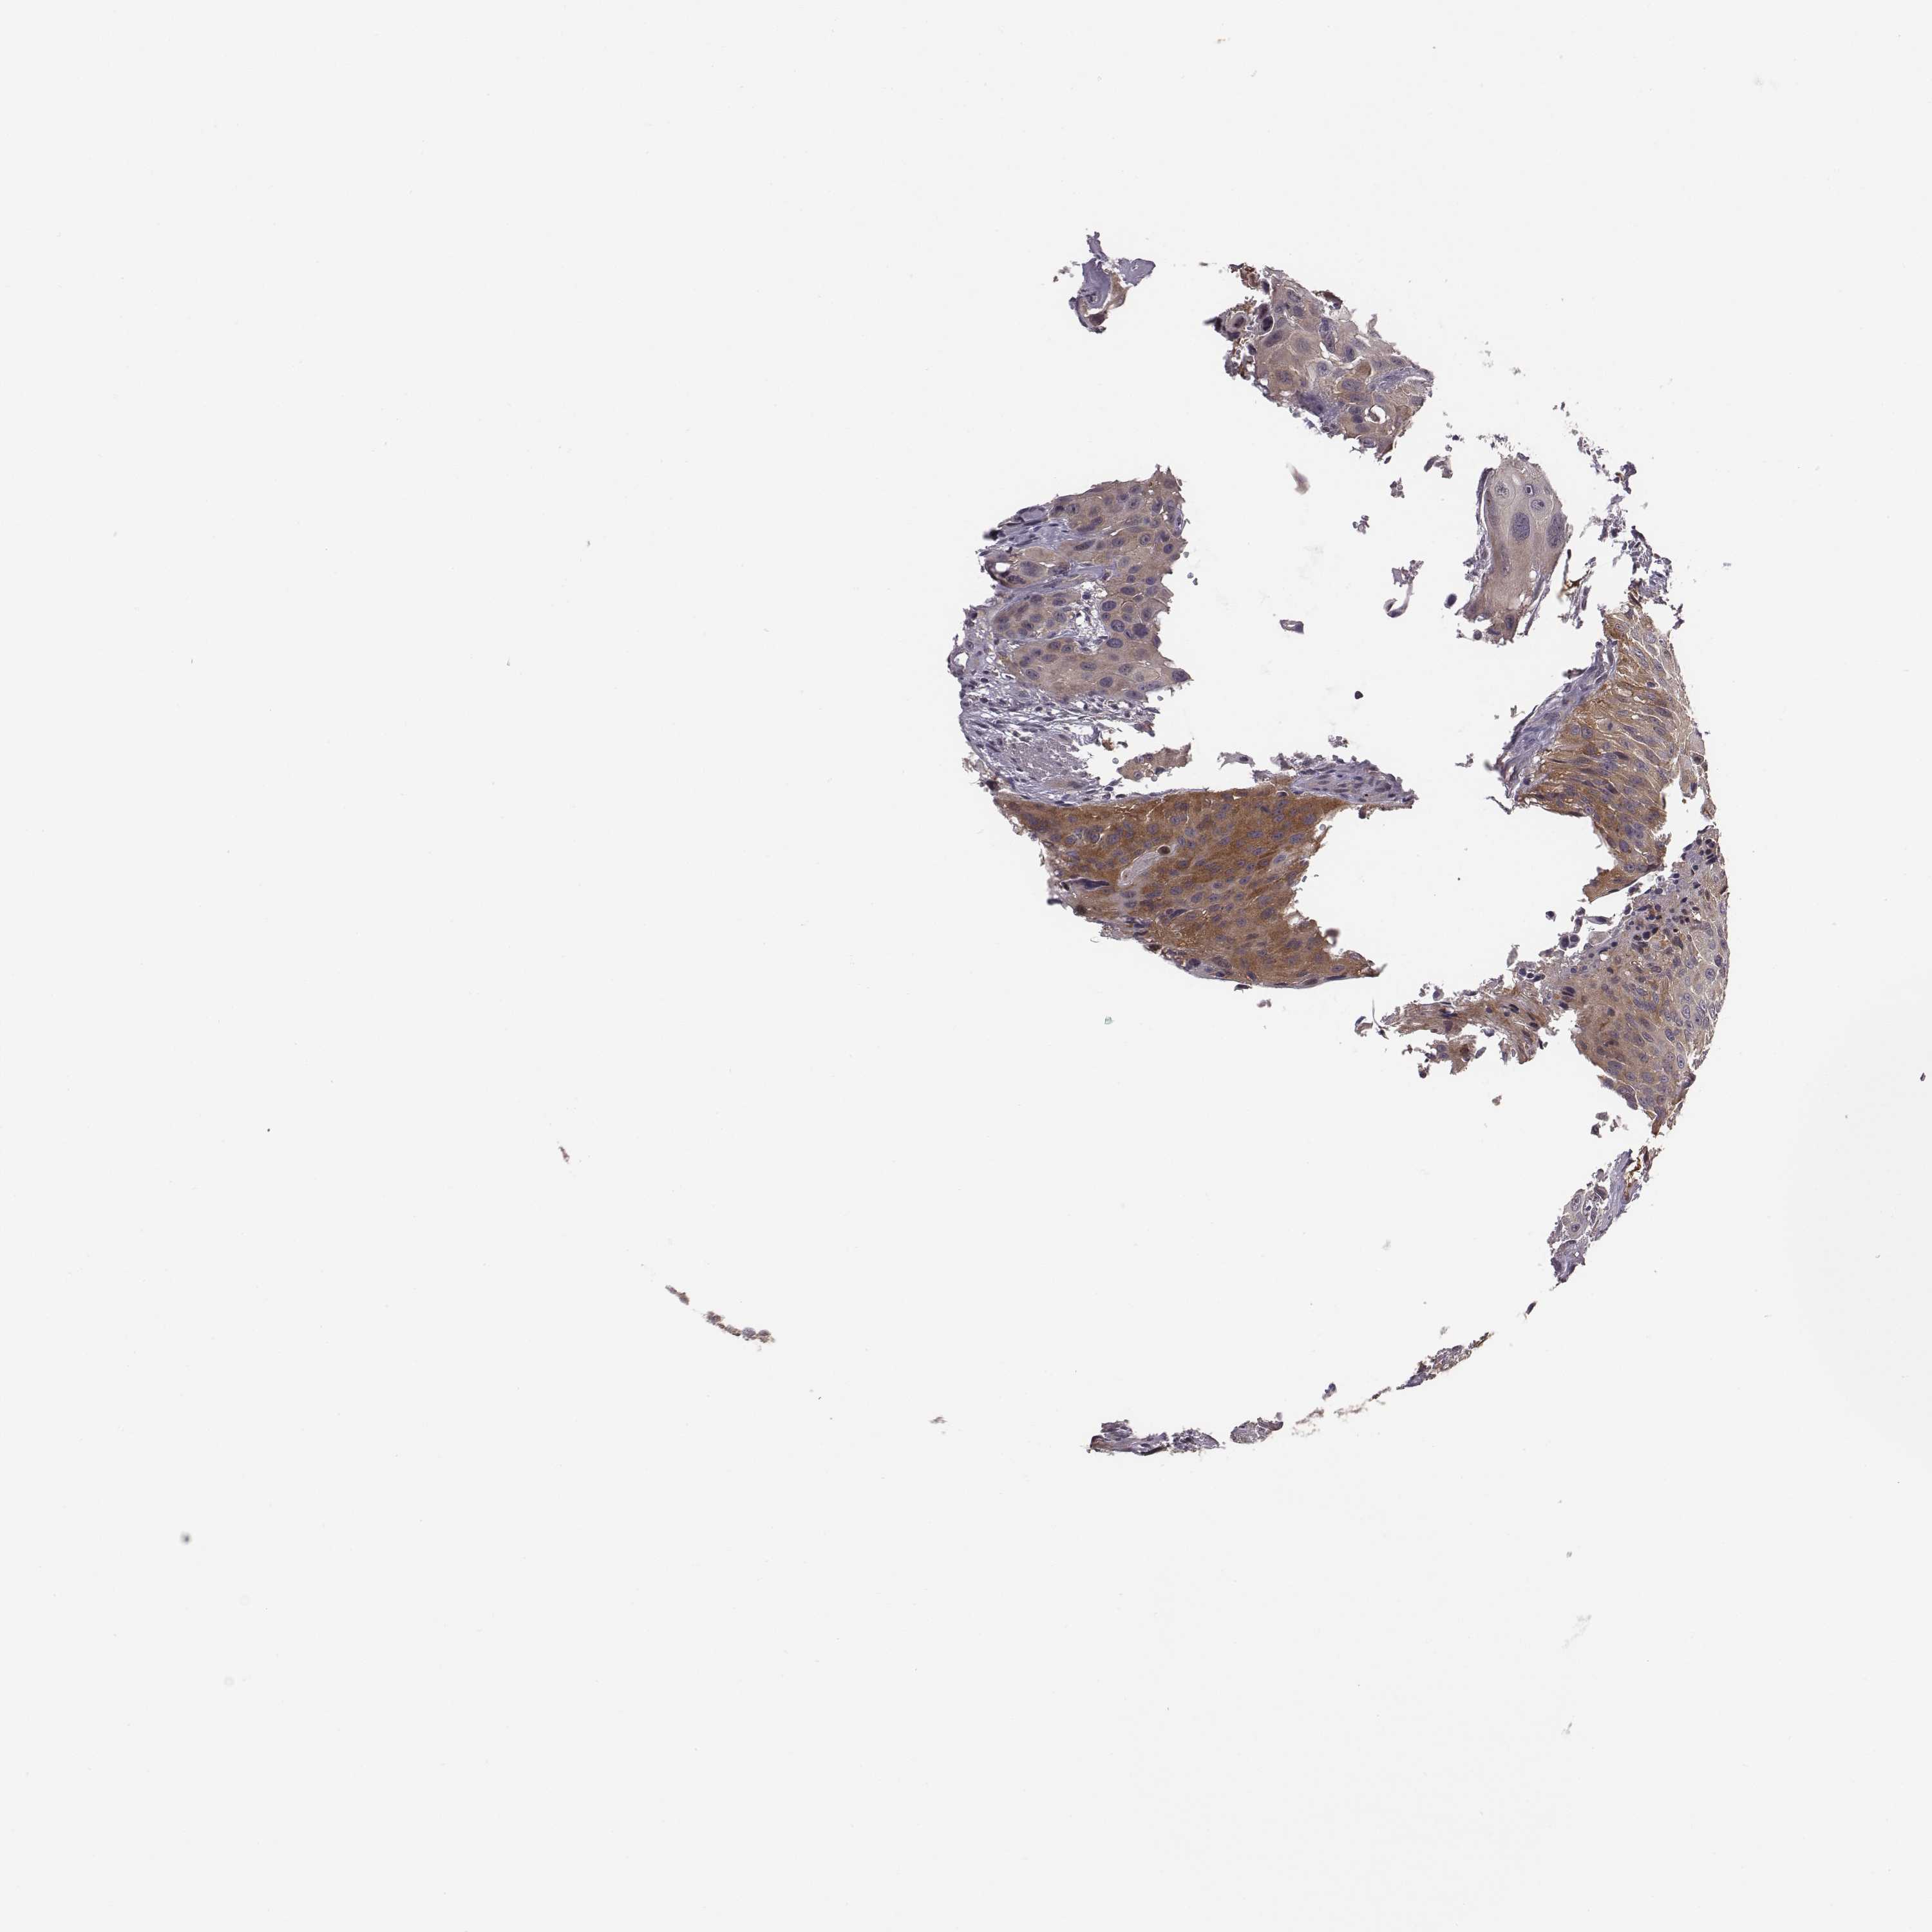

UROTHELIAL CANCER - Protein expressioni

A mouse-over function shows sample information and annotation data. Click on an image to view it in a full screen mode. Samples can be filtered based on level of antibody staining by selecting one or several of the following categories: high, medium, low and not detected. The assay and annotation is described here.

Note that samples used for immunohistochemistry by the Human Protein Atlas do not correspond to samples in the TCGA dataset.

Antibody stainingi

Antibody staining in the annotated cell types in the current human tissue is reported as not detected, low, medium, or high, based on conventional immunohistochemistry profiling in selected tissues. This score is based on the combination of the staining intensity and fraction of stained cells.

Each image is clickable and will lead to virtual microscopy that enables deeper exploration of all samples and also displays staining intensity scores, fraction scores and subcellular localization as well as patient and tissue information for each sample.

Antibody HPA071508

Staining

High

Medium

Low

Not detected

Intensity

Strong

Moderate

Weak

Negative

Quantity

>75%

75%-25%

<25%

None

Location

Nuclear

Cytoplasmic/membranous

Cytoplasmic/membranous,nuclear

Urothelial carcinoma, High grade

Urothelial carcinoma, NOS

Urothelial carcinoma, Low grade